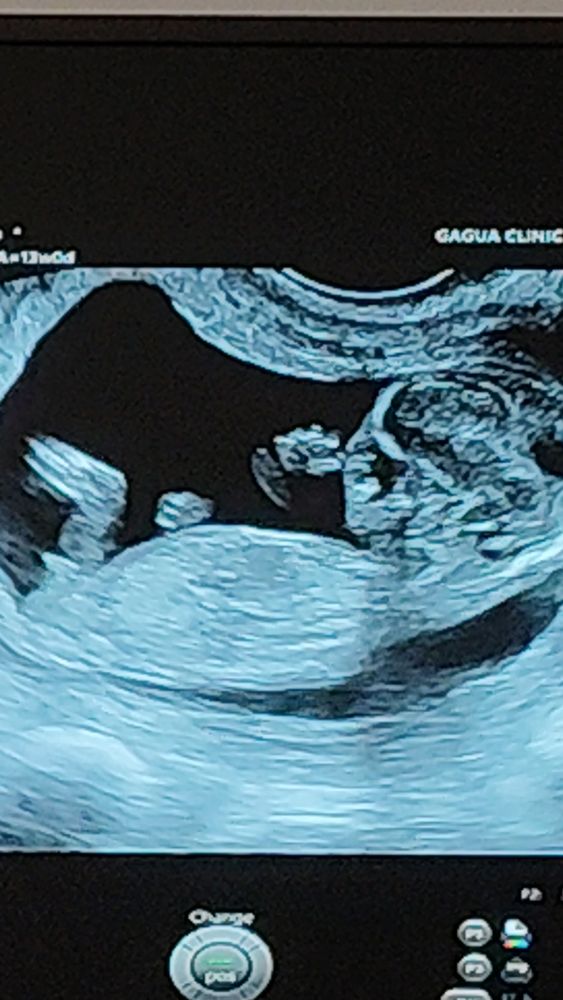

Определение пола на 13 неделе

черепаший хвостик три сына всегда лучше чем два

Наталья, узист тоже сказал что на мальчика похож

А мне кажется девочка, половой бугорок у мальчика вроде более вздренут

По половому бугорку похоже на девочку

Valeri, да я посмотрела картинки и тоже так думаю но узист сказал что похож на мальчика ❤️